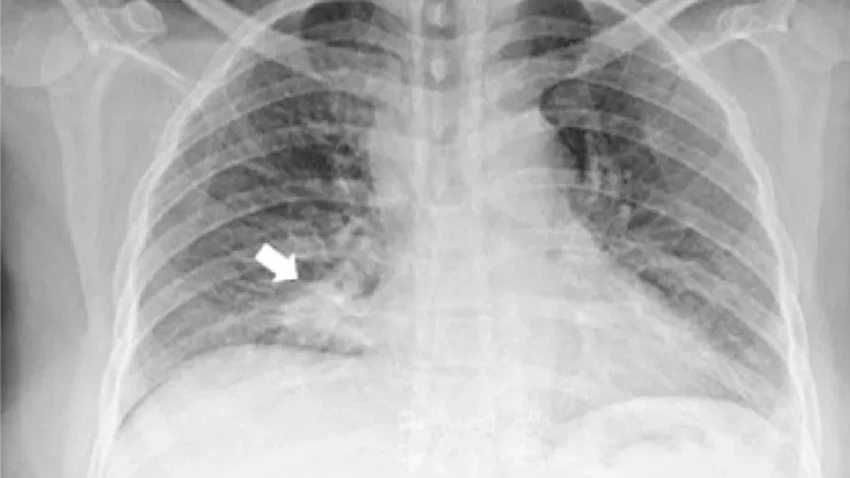

Врачи решили проверить легкие. Почему? Иногда такие глазные проблемы вызывает, например, туберкулез. Они сделали рентген грудной клетки. И картина прояснилась с пугающей ясностью: в легких зияла активная злокачественная опухоль.